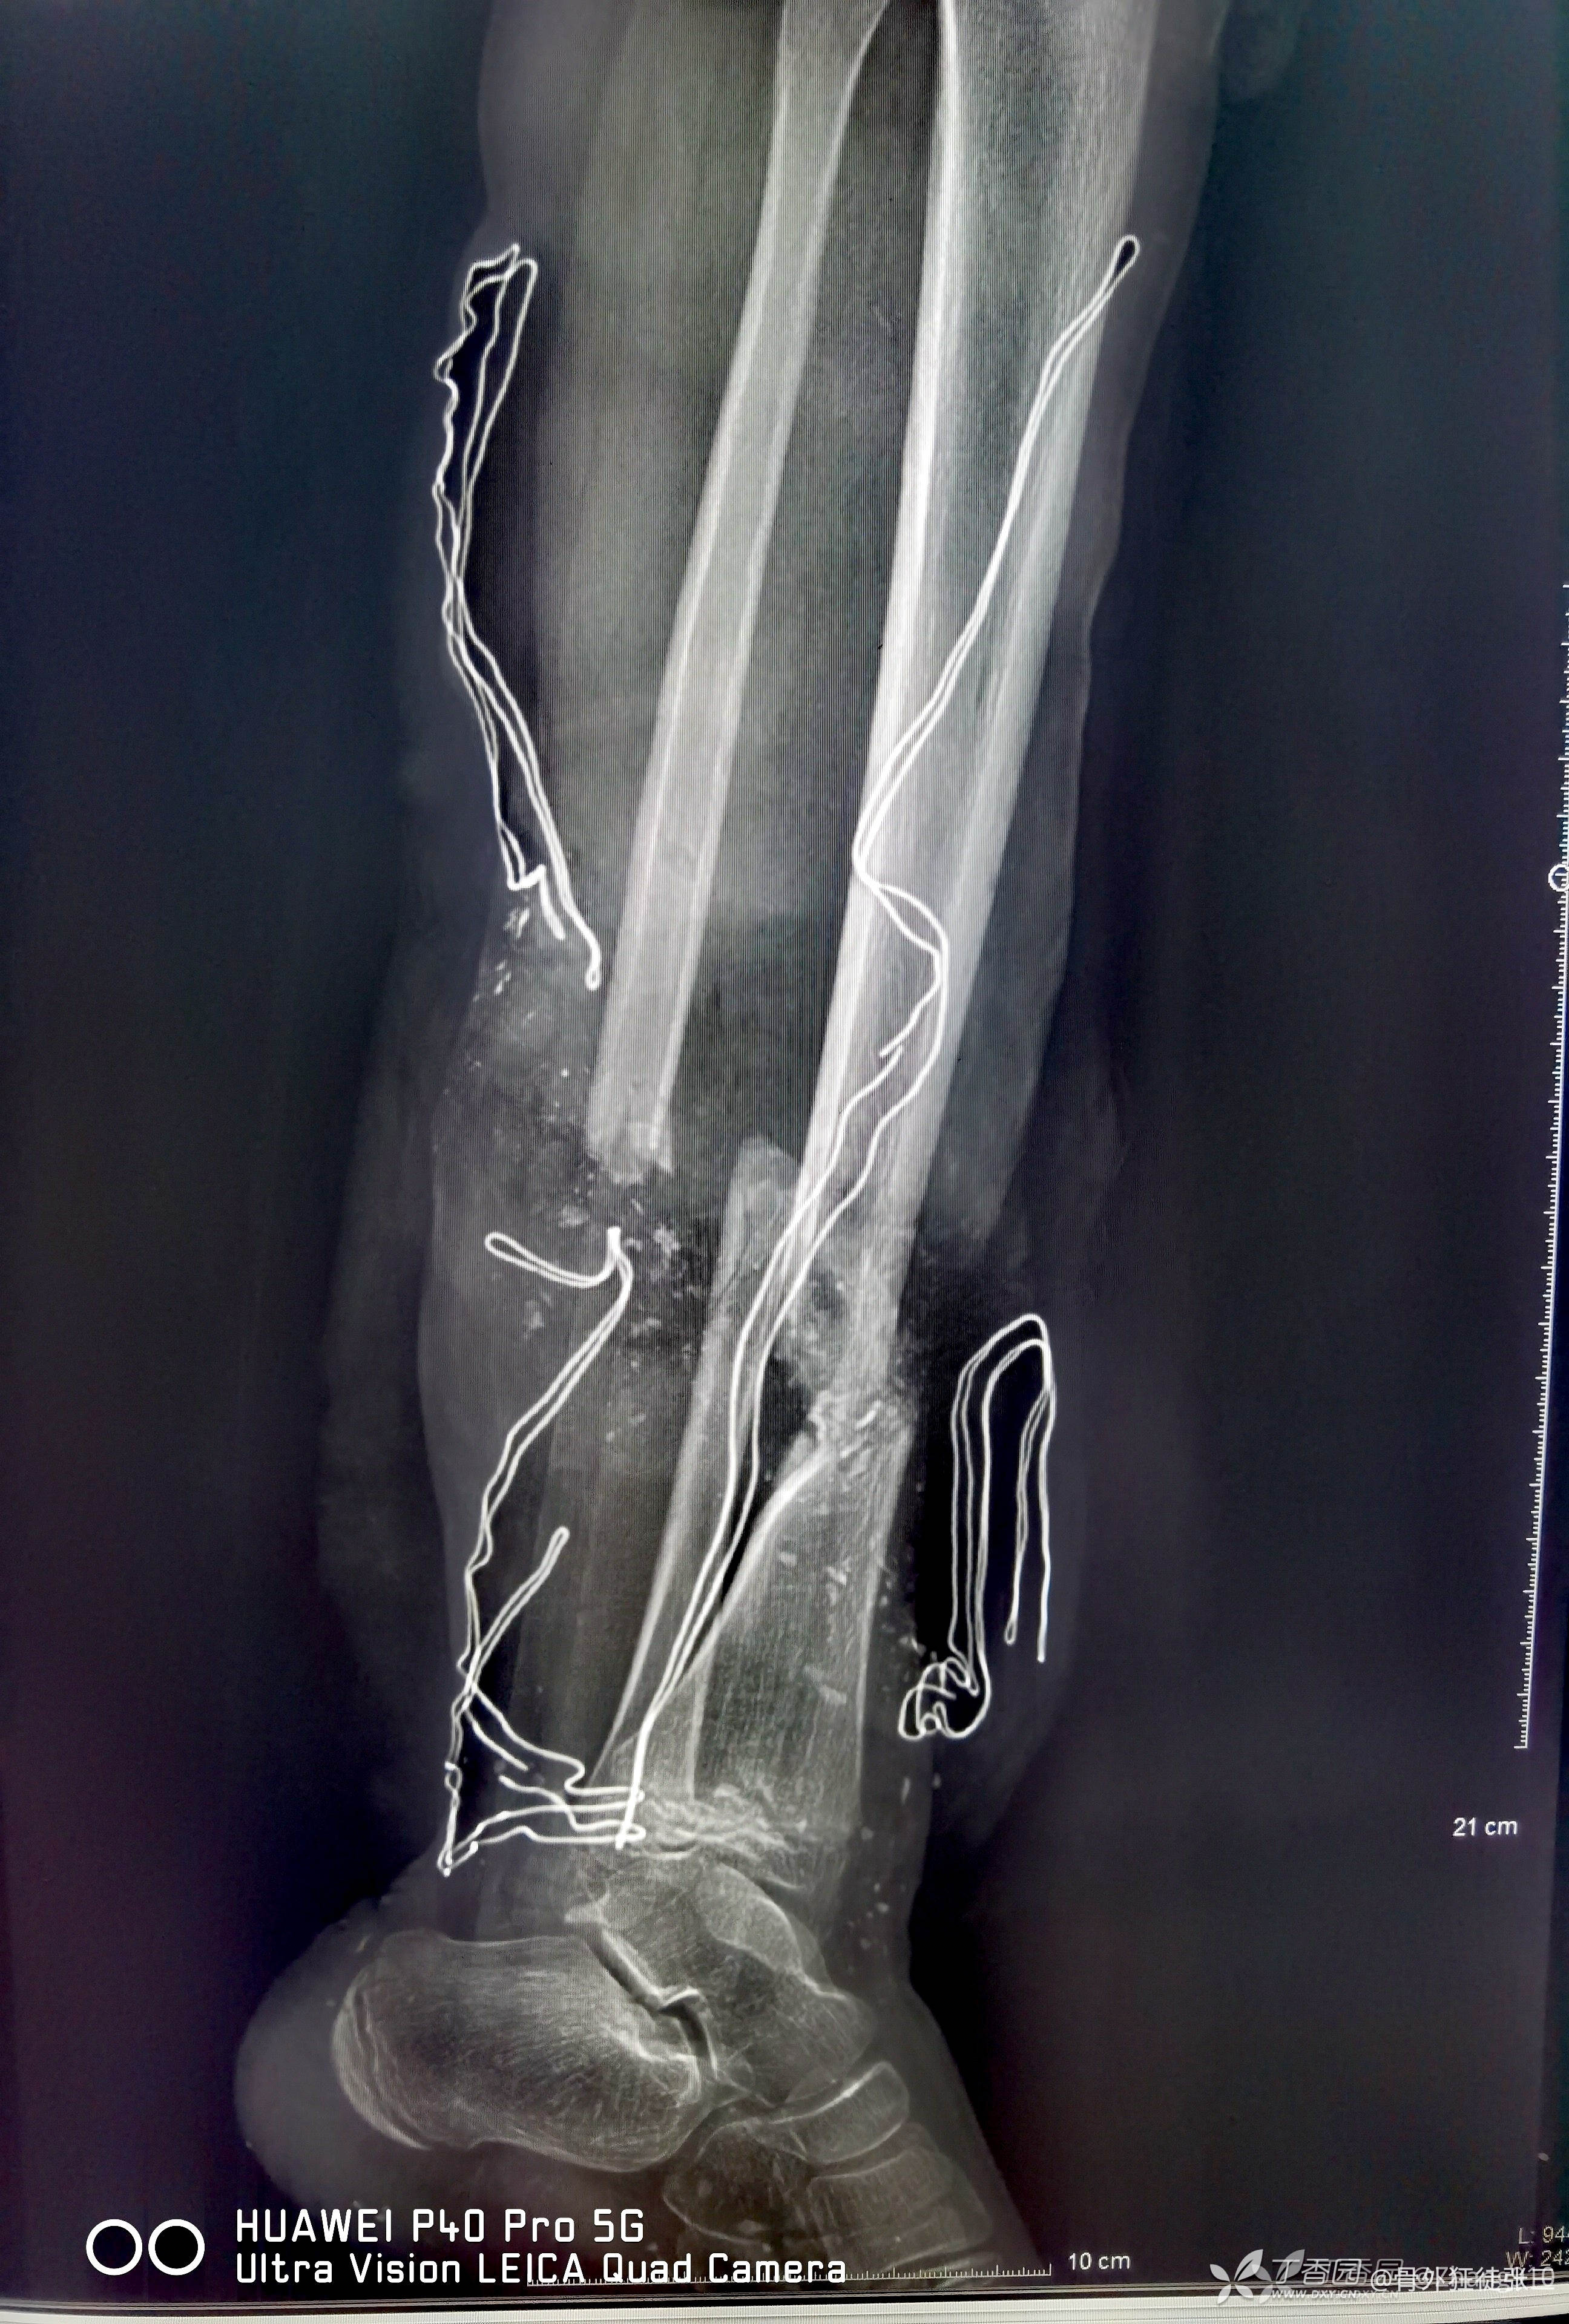

更换钢板+植骨+皮瓣整形术

腓骨未处理

第二次手术后,踝关节中立

胫骨骨折愈合

腓骨假关节形成